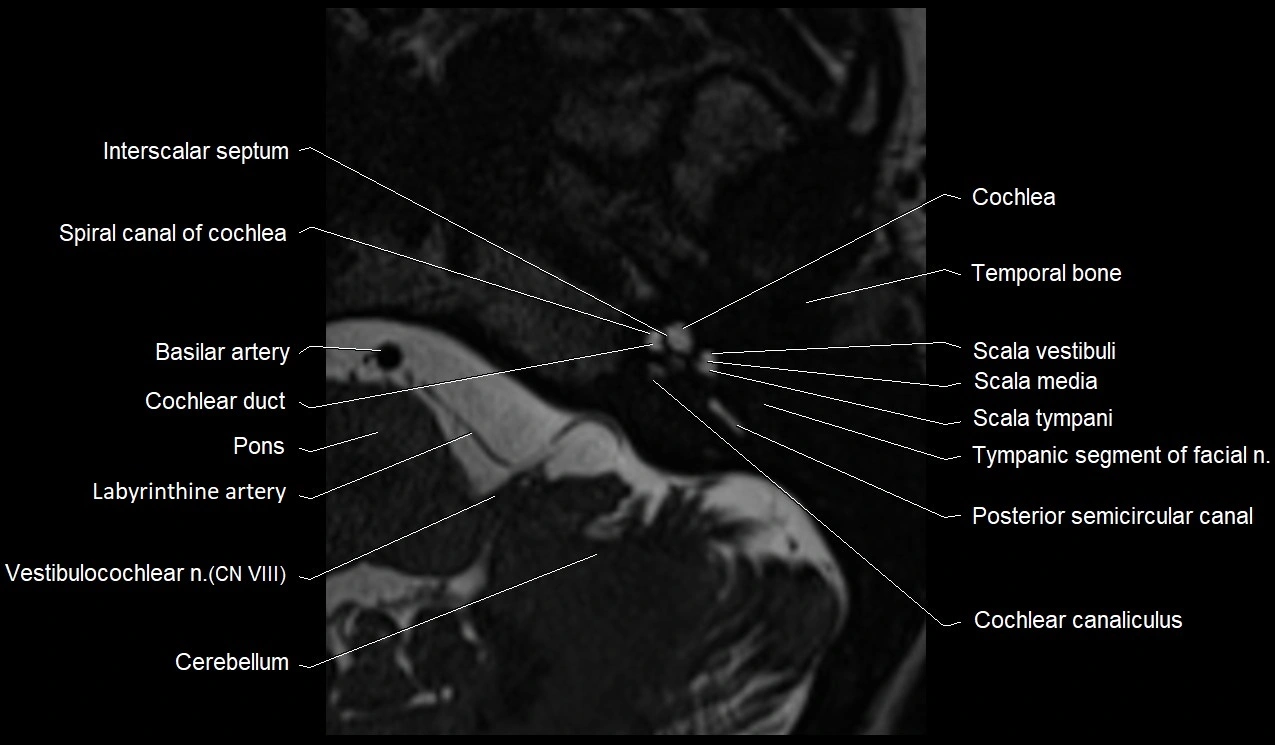

MRI Appearance

• The abducens nerve is a small, thin, linear structure

• Best visualized on high-resolution T2-weighted 3D MRI sequences (e.g., FIESTA or CISS)

• Seen as a hypointense (dark) line running from the brainstem at the pontomedullary junction, traversing the prepontine cistern, and entering Dorello’s canal under the petrosphenoidal ligament, then into the cavernous sinus, and finally the orbit

• May be challenging to visualize in standard MRI due to its small size

• Pathology may be inferred by absence, displacement, or enhancement of the nerve

MRI images

image